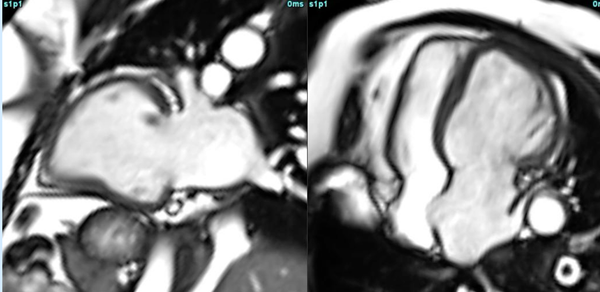

COD 175 - When a Mother’s Large Heart Becomes Normal

Peripartum cardiomyopathy is a complex condition where CMR has a role to play